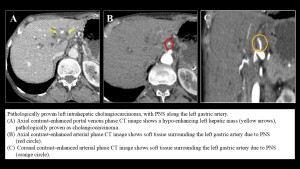

- In intrahepatic tumors, right-lobe lesions spread along the common hepatic artery, while left-lobe lesions follow the left gastric artery. Both pathways ultimately lead to involvement of celiac ganglia.

Gastric cancer may exhibit PNS through perivascular nerve plexuses associated with the left gastric artery, common hepatic artery, and celiac artery.